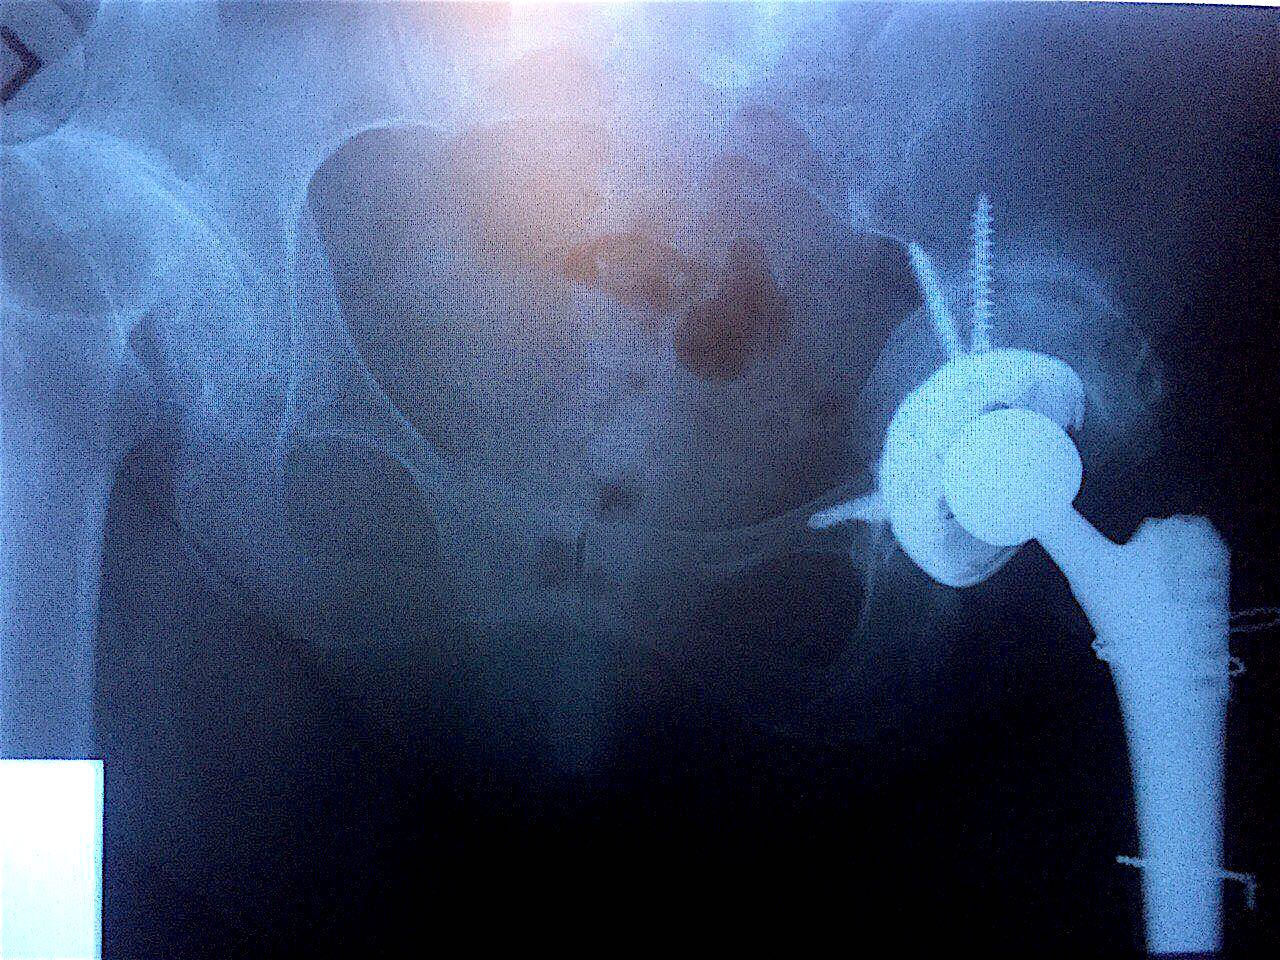

Сделано тотальное эндопротезирование левого тазобедренного сустава с компенсацией дефицита вертлужной впадины костным аллотрансплантатом «Лиопласт» (в количестве 10 шт. губчатых блоков 3х3х1 см).

Результат через 7 месяцев после операций